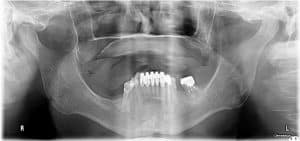

Rehabilitation of a patient with a severely resorbed maxilla using zygomatic dental implants and a novel prosthetic design for a full-arch zirconia rehabilitation

Introduction Historically, reconstruction of the severely atrophic maxilla has required multiple grafting procedures to restore lost soft and hard tissues.1,2 The most common approach involves iliac